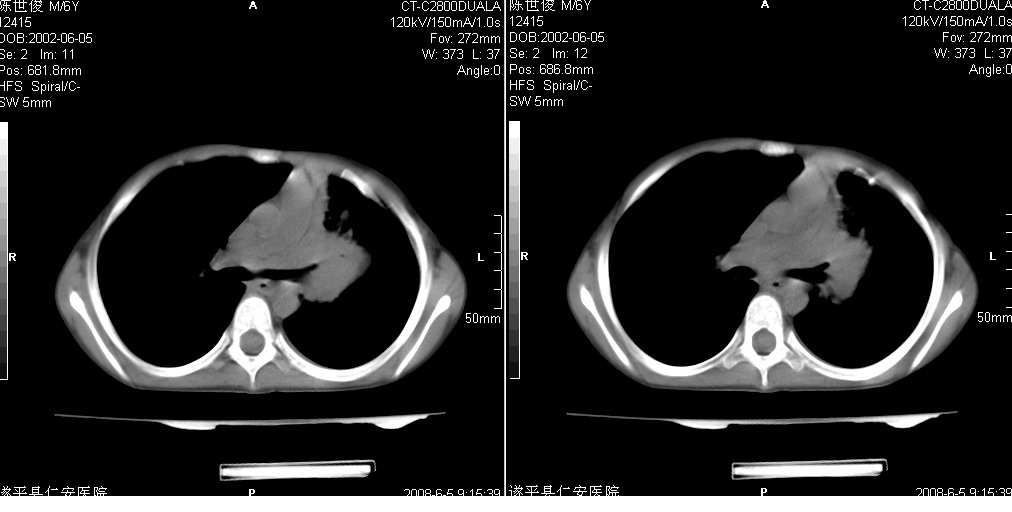

以下是引用xxhwh在2008-6-10 18:40:00的发言:[br]男,6岁,无规则发热一月余,体温在37.8——39度之间。一月前拍胸片示左上肺密度增高影,进行抗炎治疗8天,复查胸片未明显吸收。又改变抗菌素继续治疗半月,照胸片示病灶吸收不明显,行ct检查[br]征象:左上肺前段呈密实影,内可见支气管气像,远侧见絮状模糊影,中上纵隔左移。[br]意见:左上肺前段膨胀不全及感染,考虑为支气管异物或支气管内膜结核所致,[br]建议追问有无异物吸入史,行痰检及ppd检查